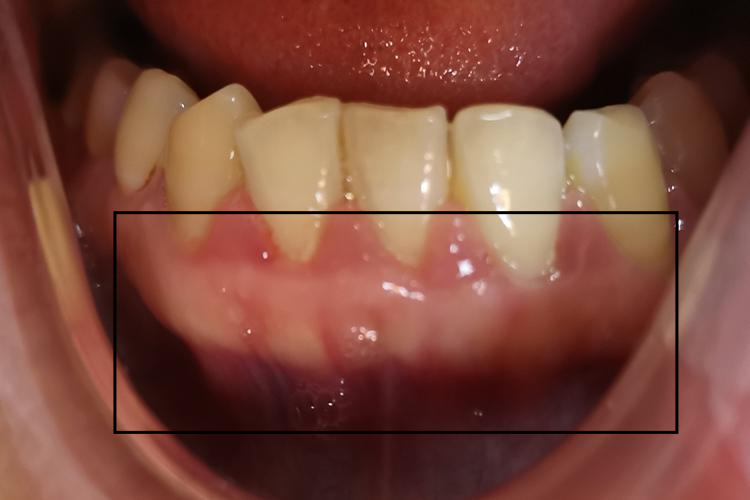

青春期龈炎

青春期龈炎好发于前牙唇侧的牙龈乳头和龈缘。患者一般因刷牙或咬硬物时出血或口臭而就诊。唇侧龈缘明显肿胀,龈乳头呈球状突起,颜色呈鲜红或暗红色,光亮,质地软,探诊易出血。龈袋形成,但无附着水平的变化。